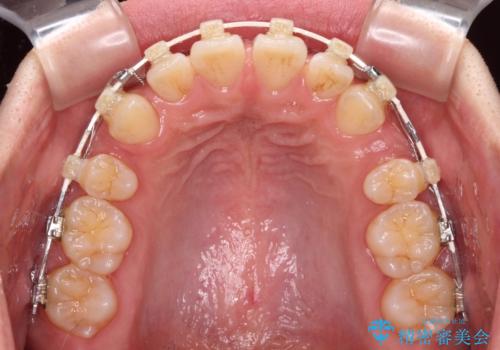

- 矯正装置

- 審美装置

- 前歯の突出感を気にして来院された患者様です。

咬合力が非常に強く、咬合力で前歯が前方に押し広げられており、上下唇に閉じにくさが認められました。

上下左右の第一小臼歯4本を抜歯し、ワイヤー装置にて矯正治療を行うこととしました。

強い咬合力により前歯の隙間がなかなか閉じられず、治療期間は長いものとなりましたが、横顔の印象が大きく変わるほど口元の印象を改善することができました。